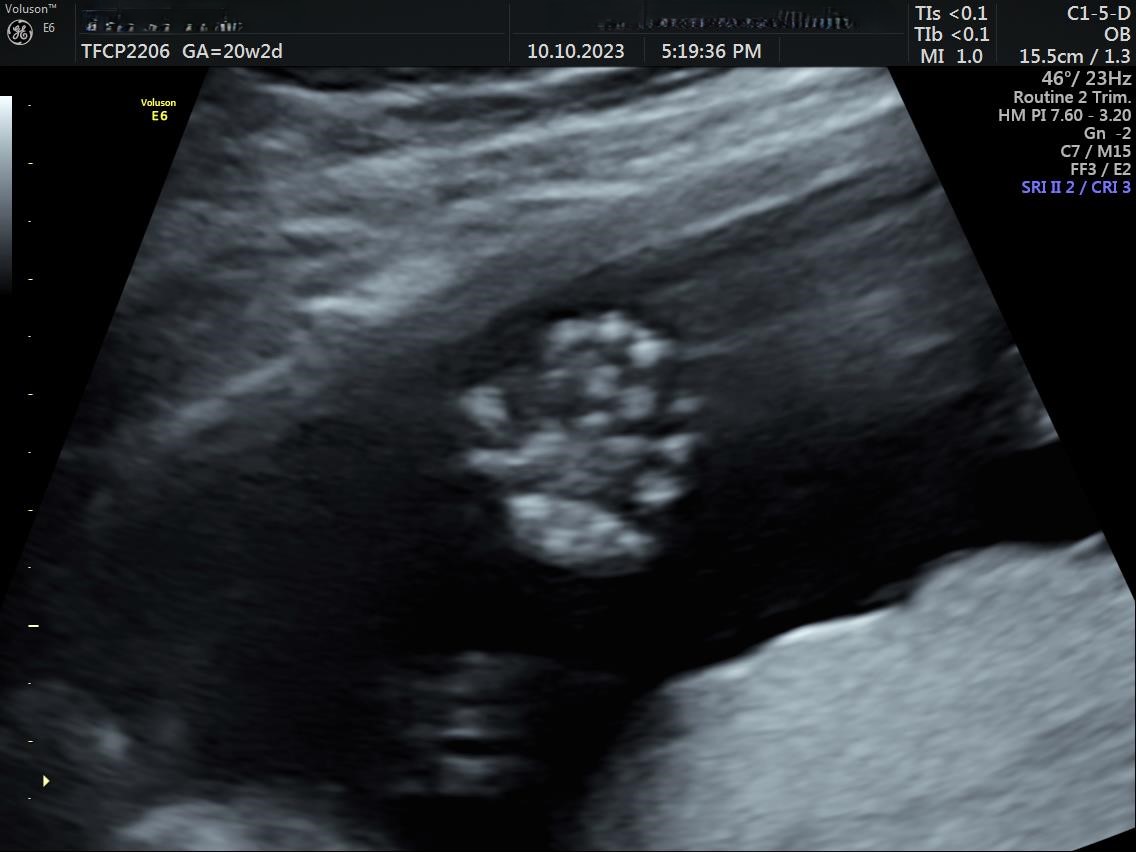

• Early anomaly & Anomaly scan(TIFFA)

• Genetic sonogram(GSG)